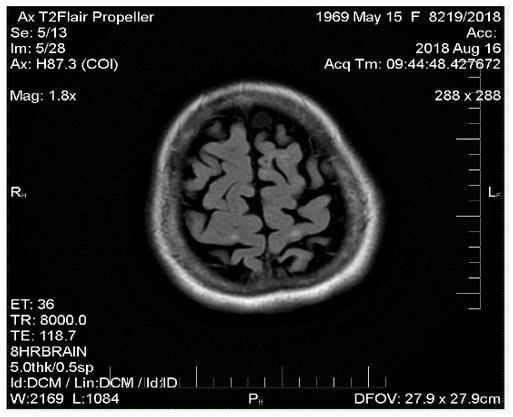

Comparing magnetic resonance recordings over time, it was determined that within a 10-year period, practically no new lesions had formed (Figure 1-3). Although the patient continues to experience some neurological interference, she remains active, fully functional, and independent. She travels frequently, has purchased a car, and drives herself. Her current neurological condition is characterized as mild paraparesis affecting the lower extremities and the right arm, yet she maintains mobility and autonomy. This review sufficiently covers her progress; no additional remarks are necessary. Conclusion stands on its own.

Figure 2 MRI image from 2018.